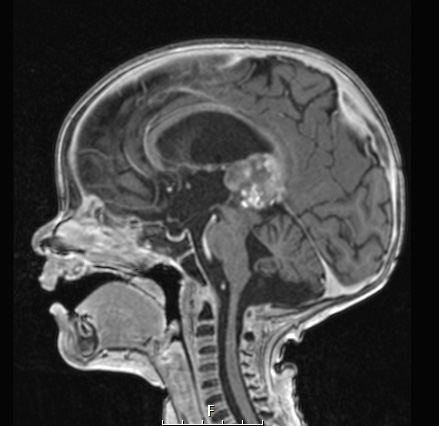

The patient is a 1yo male who presented to an outside hospital with a pineal region enhancing mass status post biopsy (called embryonal neoplasm, favor pineal anlage tumor, and matching to pineoblastoma on methylation profiling) status post chemotherapy who presented for re-resection. Operative procedure: Craniotomy for resection of midline left sided mass, possible placement of an external ventricular drain

2A The pineal neoplasm shows variegated enhancement in this T1-weighted contrast administered scan.